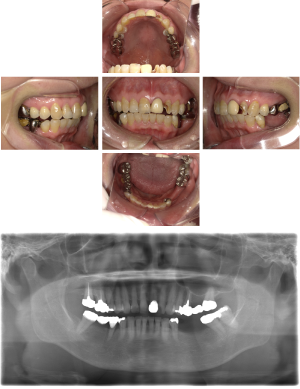

30代 女性 奥歯 インプラント

| 年代・性別 | 30代・女性 |

| 治療回数 | 10回(術前治療・検査除く) |

| 治療期間 | 約1年 |

| 料金 | ¥410,300(税込)※別途検査料 |

失った歯を補うために、インプラント治療は優れた治療方法です。 しかし、全ての人にインプラント治療が優れている治療ではありません。 |

| 副作用 | 術後に腫れ・痛みが出る可能性がある。 |